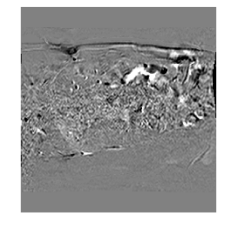

Fig. 4 shows a comparison of a representative motion field predicted by MFINc with that computed via the GS registration algorithm. We can see that the motion field produced by MFINc is smooth and has sharper motion boundaries. The reason for this might be that the used registration is more regularized due to its parametric model, where motion is defined by a grid of control points with 4x4 pixel spacing and linearly interpolated in between. This might also explain the higher error in evaluation of the flow field predicted by the network over the whole image (RefMotErrFl) than only over the liver (RefMotErrFlLiver).

aRefer to caption bRefer to caption cRefer to caption dRefer to caption

Figure 4: (a) Motion field 𝐅tt+1subscript𝐅𝑡𝑡1\mathbf{F}_{t\to t+1} from MFINc-SSIM overlaid on Nt+1subscript𝑁𝑡1N_{t+1}-Ntsubscript𝑁𝑡N_{t} and (b) corresponding motion magnitude image. (c) 𝐅tt+1gssubscriptsuperscript𝐅𝑔𝑠𝑡𝑡1\mathbf{F}^{gs}_{t\to t+1} from gold standard registration and (d) its magnitude image.